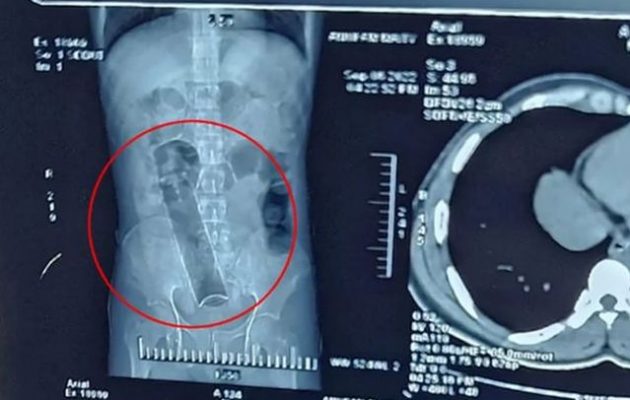

Έτσι, μόλις έγινε εισαγωγή, οι γιατροί πραγματοποίησαν αρκετές ακτινογραφίες και είδαν πως είχε σφηνώσει στον πρωκτό του ένα αποσμητικό περίπου 19 εκατοστών, το οποίο βρίσκονταν εκεί για περίπου 20 μέρες, με αποτέλεσμα να μην μπορεί να πάει στην τουαλέτα.